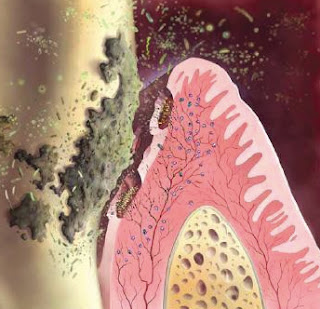

قبل عدة شهور زارني مريض يشكو من تورم في اللثة, كان المريض قد قام بخلع الضرس في احد المراكز وكان يشك ان الورم زاد بسبب الخلع لكن لم يكن يشتكي من اي ألم. بعد الفحص قمت بتحويل المريض لعمل اشعة للفم حيث ان الورم لم يكن عاديا, اظهرت الأشعة ان التورم ما هو الا نمو سرطاني وعلى ما يبدو فإن الورم كان موجودا سابقا وان الطبيب الذي عالجه أولا كان يعتقد انه مجرد خراج عادي ولم يتحقق من سبب الورم جيدا. قمت بتحويل المريض الى المستشفى لاستئصال نسيج من الأنسجة وفحصه لتحديد نوع الورم وطلبت من المريض ان يطلعني على نتيجة الفحص عندما يحصل عليها. مرّ وقت طويل دون ان يرجع المريض ونسيت الموضوع.

بعد بضعة شهور عاد المريض الى العيادة وقد زادت الحالة سوءا, لقد زاد حجم الورم حتى غطّى نصف الفك العلوي تقريبا كما امتد الى الحلق واصبح يسبب صعوبة في البلع. بالإضافة الى ذلك تكونت قرحة كبيرة مقززة على سطح الورم.